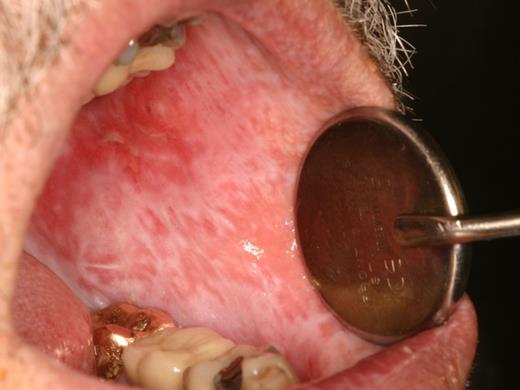

Patients with salivary gland cGVHD are at risk for developing secondary infectious complications because of diminished anticariogenic and antifungal activities. In addition to the effects on teeth (Figure 7), patients are at significant risk for recurrent oral candidiasis, especially if there is ongoing topical corticosteroid therapy for management of mucosal cGVHD, which suppresses mucosal immunity (see “Infections”; Figure 8).

Rampant cervical dental caries affecting all of the teeth in a patient with cGVHD of the salivary glands. Demineralization changes (arrow) appear chalky white.

Dental caries

Patients with salivary gland cGVHD are at risk for developing secondary infectious complications because of diminished anticariogenic and antifungal activities. The development of accelerated and often rampant dental caries is a largely under-recognized complication of oral cGVHD that can develop rapidly, leading to extensive dental treatment, extraction of teeth, and significant social and economic costs.65-67 Before the development of frank carious lesions, the teeth may demonstrate demineralization changes along the cervical margins, characterized by a white and chalky appearance (Figure 7). Dental caries tend to develop at the cervical margins and interproximal surfaces where dental plaque accumulates because of lack of salivary flow. Exacerbating this problem is that patients with oral mucosal cGVHD may neglect oral hygiene because of discomfort associated with tooth brushing, compounding the effects of salivary gland changes. In addition to the effects on teeth, patients with salivary gland cGVHD are at significant risk for recurrent oral candidiasis, especially if there is ongoing topical corticosteroid therapy.

Prevention of dental caries is a critical component of salivary gland cGVHD management, and we initiate these measures in all patients with clinically significant disease (Table 4). Patients should be continuously reminded of the importance of maintaining a noncariogenic diet and good oral hygiene. In patients with severe salivary gland hypofunction, even when tooth brushing after eating is not feasible, patients should be instructed to rinse their mouths well with water. Prescription 1.1% sodium fluoride gel should be applied to the teeth nightly, either using a toothbrush to “paint on” to the teeth, or via custom-fitting trays that can be fabricated by the patient's dentist.68,69 In addition to topical fluoride, emerging evidence supports the use of a calcium/phosphate-based remineralizing agent (eg, GC MI Paste Plus, GC America), which can be applied just before topical fluoride.70,71 Dentists can place fluoride varnish twice annually during recall visits for further protection. Bitewing radiographs should be obtained on an annual basis to screen for interproximal decay (Figure 15), and areas of decay should be treated promptly and definitively (ie, the full extent of caries must be removed as risk for recurrent decay is high).